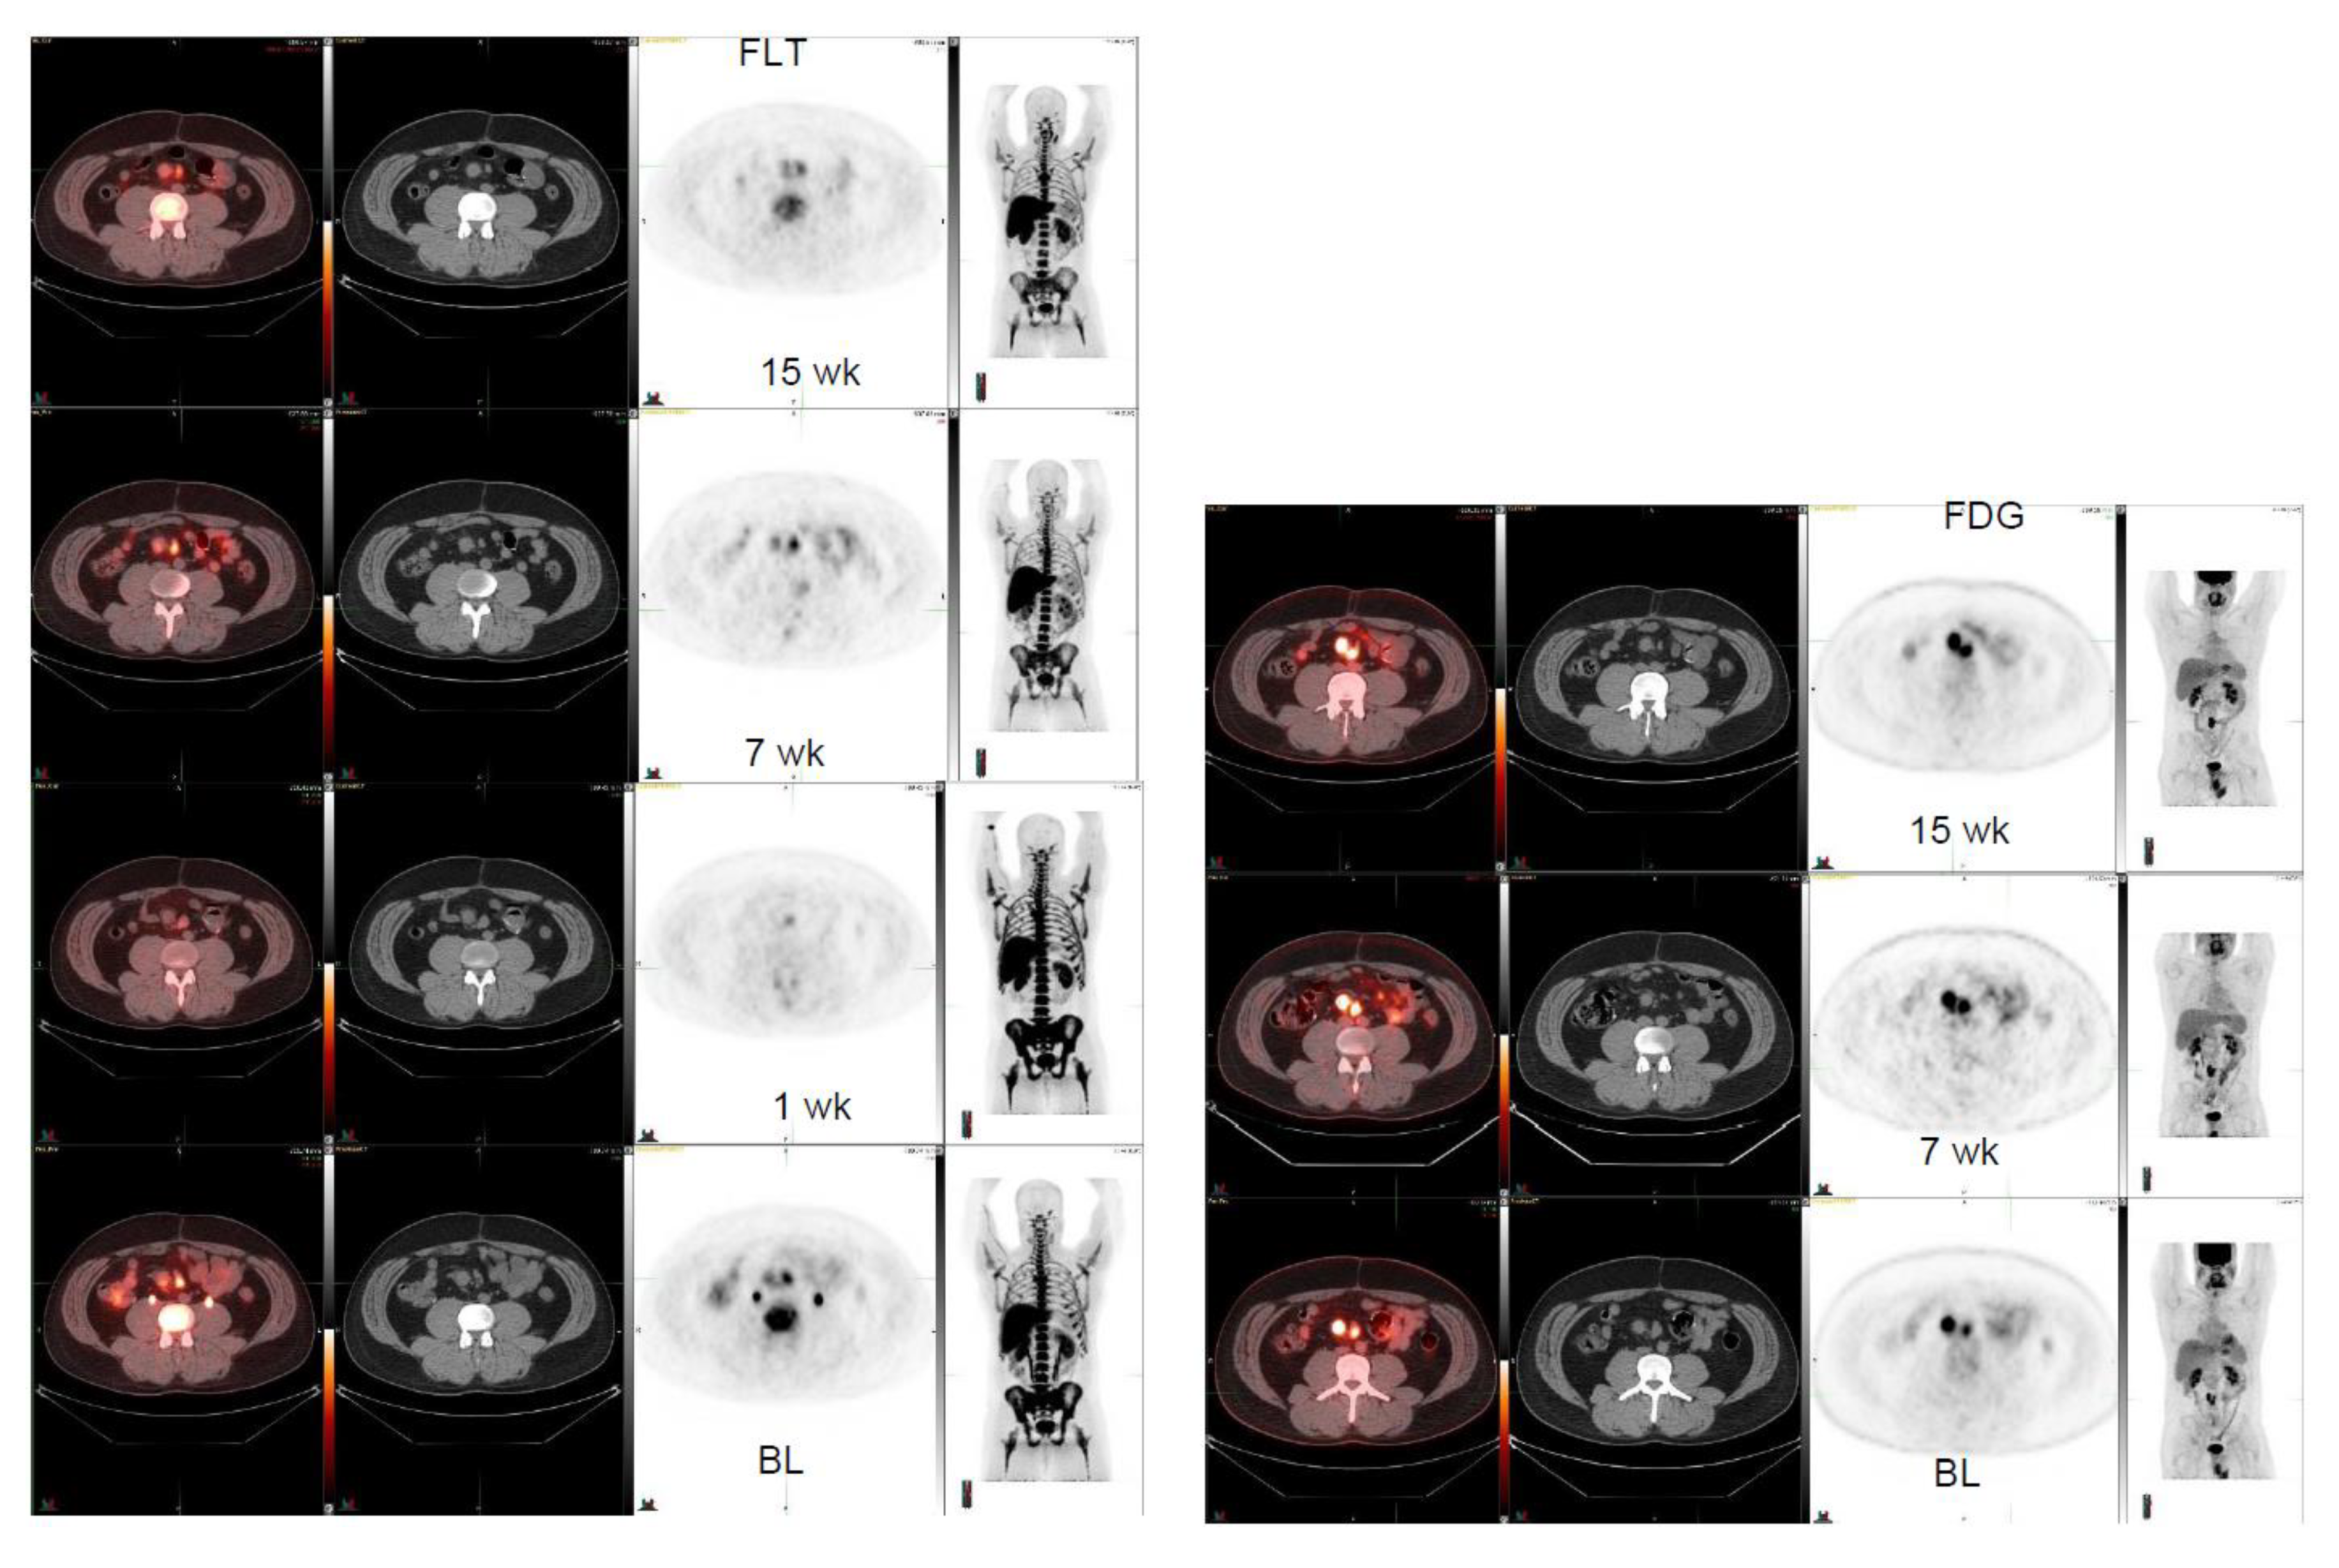

| 32/ M | GNET, mesenteric lnn R | 5.2 2.2 × 1.9 12.9 | 3.9 2.0 × 2.0 15.4 7 weeks | 2.8 1.9 × 1.7 10.6 15 weeks | 3.2 (1 week) 2.0 × 1.8 (1 week) FDG | −25%+19% |

| 32/ M | GNET, mesenteric lnn L | 5.5 2.3 × 1.1 8.2 | 5.9 2.1 × 1.4 9.9 7 weeks | 4.0 2.0 × 1.2 8.0 15 weeks | 3.4 (1 week) 1.9 × 1.5 (1 week) FDG | +7% +21% |